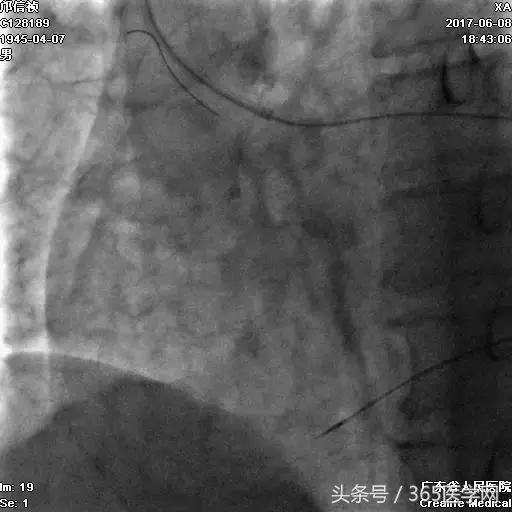

支架术后造影结果

支架术后IVUS

小结

CTO介入前要认真读图,详细制定介入策略及步骤,

明确IVUS在CTO介入的重要性,

Guidezilla辅助下的ReverseCART更加高效,

Knuckle导丝技术在CTO介入中的使用。